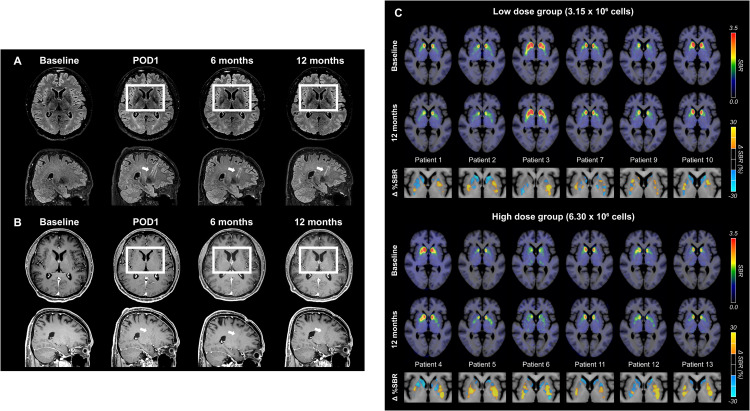

安全性验证:根据术后影像学评估,人胚胎干细胞衍生的A9-DPC疗法在帕金森病患者中显示出积极结果。首先,安全性与移植准确性得到确认:脑部MRI扫描显示,移植部位未出现肿瘤或炎症迹象(图S4A和S4B),针道轨迹证实细胞被精确递送至目标区域——壳核;同时,¹⁸F-FDG PET未检测到细胞的异常增殖或迁移,共同证明了该疗法的解剖精准性和短期安全性。

细胞存活与功能整合:在细胞存活与功能整合方面,连续的多巴胺转运体(DAT)影像(¹⁸F-FP-CIT PET)提供了关键证据。数据显示,移植后12个月,作为主要功能指标的后背壳核区的DAT特异性结合率(SBR)呈现剂量依赖性增加,高剂量组的变化尤为显著:高剂量组中位增长10.7%(p=0.041),低剂量组增长1.0%。

这一结果表明,移植的细胞不仅存活,而且成功在关键脑区建立了新的多巴胺能神经支配。

(A)纹状体中的18 F-FP-CIT SBR 图像。图中显示了所有参与者(n = 12)在基线和 A9-DPC 移植后 12 个月的平均18 F-FP-CIT SBR 的轴向图像。SBR 图像以小脑灰质为参考组织生成。SBR 的计算方法是将每个体素与参考区域的摄取值之差除以参考区域的摄取值。 (B)基线和 A9-DPC 移植后 12 个月的组平均18 F-FP-CIT SBR 图像。图中显示了低剂量组和高剂量组基线和移植后 12 个月的平均18 F-FP-CIT SBR 的轴向图像。SBR 图像以小脑灰质为参考组织生成。SBR 的计算方法是将每个体素与参考区域的摄取值之差除以参考区域的摄取值。 (C) 18 F-FP-CIT SBR的区域变化。图中显示了每个亚区域低剂量组和高剂量组从基线到 12 个月的 SBR 百分比变化。箱线图显示中位数(水平线)、IQR(箱线图)和全范围(须线图),并叠加了个体患者值。使用 Wilcoxon 秩和检验计算组间比较的p值。